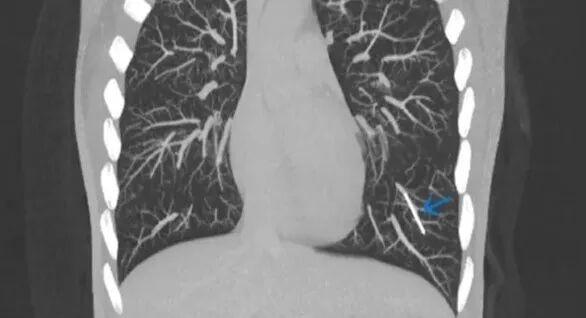

通過CT檢查,醫生在一位英國女性的肺裏發現了意想不到的東西:一根失蹤多年的避孕植入物[8]

用於避孕的皮下埋植物通常很安全,但在罕見的情況下,它也有可能在人體內遊走,甚至到達肺部。圖中藍色箭頭標記的小棒就是進入肺部動脈的“流浪植入物”。 | Kareem et al.

這種植入物是火柴大小的彈性棒狀物,它原本應該埋植在使用者手臂的皮下,通過緩慢釋放孕激素髮揮避孕功能。皮下埋植是效果最可靠的避孕手段之一,但在罕見的情況下,植入物有可能會在體內移位。

在這位女患者體內,植入物卡在了左下肺的一段動脈裏。它應該是首先進入了手臂的靜脈,然後順着血液迴流來到心臟,最後到達了肺部。醫生推測,這種情況可能與植入時操作不當有關。